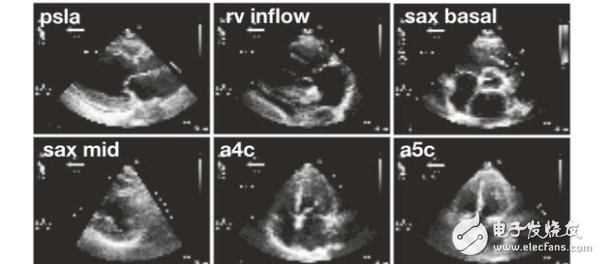

7300 這個(gè)星球上的人們,或許還沒有做好迎接人工智能醫(yī)生的準(zhǔn)備。不過,加州大學(xué)舊金山分校(UCSF) 的研究人員培育的AI,已經(jīng)在心臟圖像的分類比賽上,超過了參賽的人類心血管醫(yī)師。

2018-03-30 11:04:19